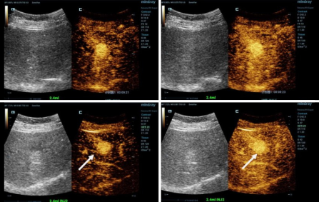

Genauere Diagnosen mit HiFR-CEUS

Kontrastmittelverstärkter Ultraschall (CEUS oder KM-Sonografie) ist ein außerordentlich dynamisches Feld, auf dem in den letzten Jahren weitere technologische Innovationen zur Verbesserung der Bildqualität erreicht werden konnten. Eine dieser Innovationen ist der kontrastmittelverstärkte Ultraschall mit hoher Bildrate (HiFR-CEUS), der im Vergleich zu herkömmlichem Ultraschall bis zu zehnmal so viele Bilder liefert – in derselben Zeit.

Ultraschall | Allgemeine Bildgebung 2022-12-16